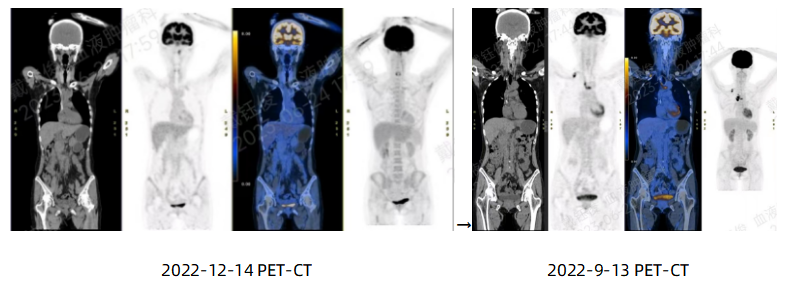

➤CAR-T回输后1个月首次疗效评价:2022-12-14查PET-CT示双颈、双侧腋窝、纵隔、右侧内乳区、双肺门、双侧隔脚后、腹腔、腹膜后、双侧髂血管旁及双侧腹股沟多个小淋巴结部分代谢略活跃,SUV约2.2,Deauville评分2分,较前好转;肝S8、S6各见一稍低密度影,代谢未见明显异常,范围较前稍缩小;左侧头长肌代谢活跃,疑生理性摄取/炎性病变;双肺多发条片影及小类结节影,代谢未见明显异常,疑炎性病变/增殖灶;双肺肺大泡;双肾多发小结石;右小腿外侧局部皮肤稍增厚,代谢略活跃,疑治疗后改变伴炎性变。疗效评估为CR。